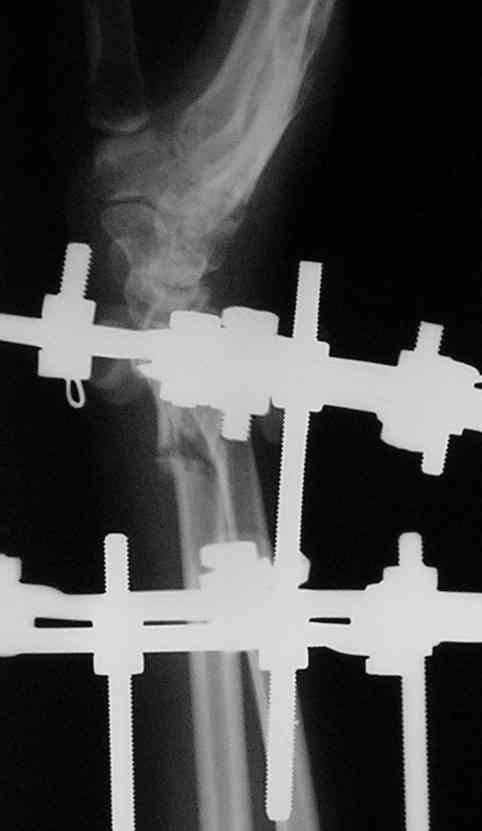

Виктор, спасибо за высланные фото и Ргграммы.

У больного/ой кроме перелома лучевой кости и шиловидного отростка локтевой, разрыв дистального радиоульнарного сочленения, перелом ладьевидной кости и ладьевидно-полулунная диссоциация.

Если позволите свое мнение, не стал бы лечить аппаратом эту травму, перелом луча не консолидировался: открытая репозиция+ костная пластика+ пластина, синтез ладьевидной кости, по возможности шов ладьевидно полулунной связки,

если восстановить связку не представляется возможным, фиксация 2 спицами.